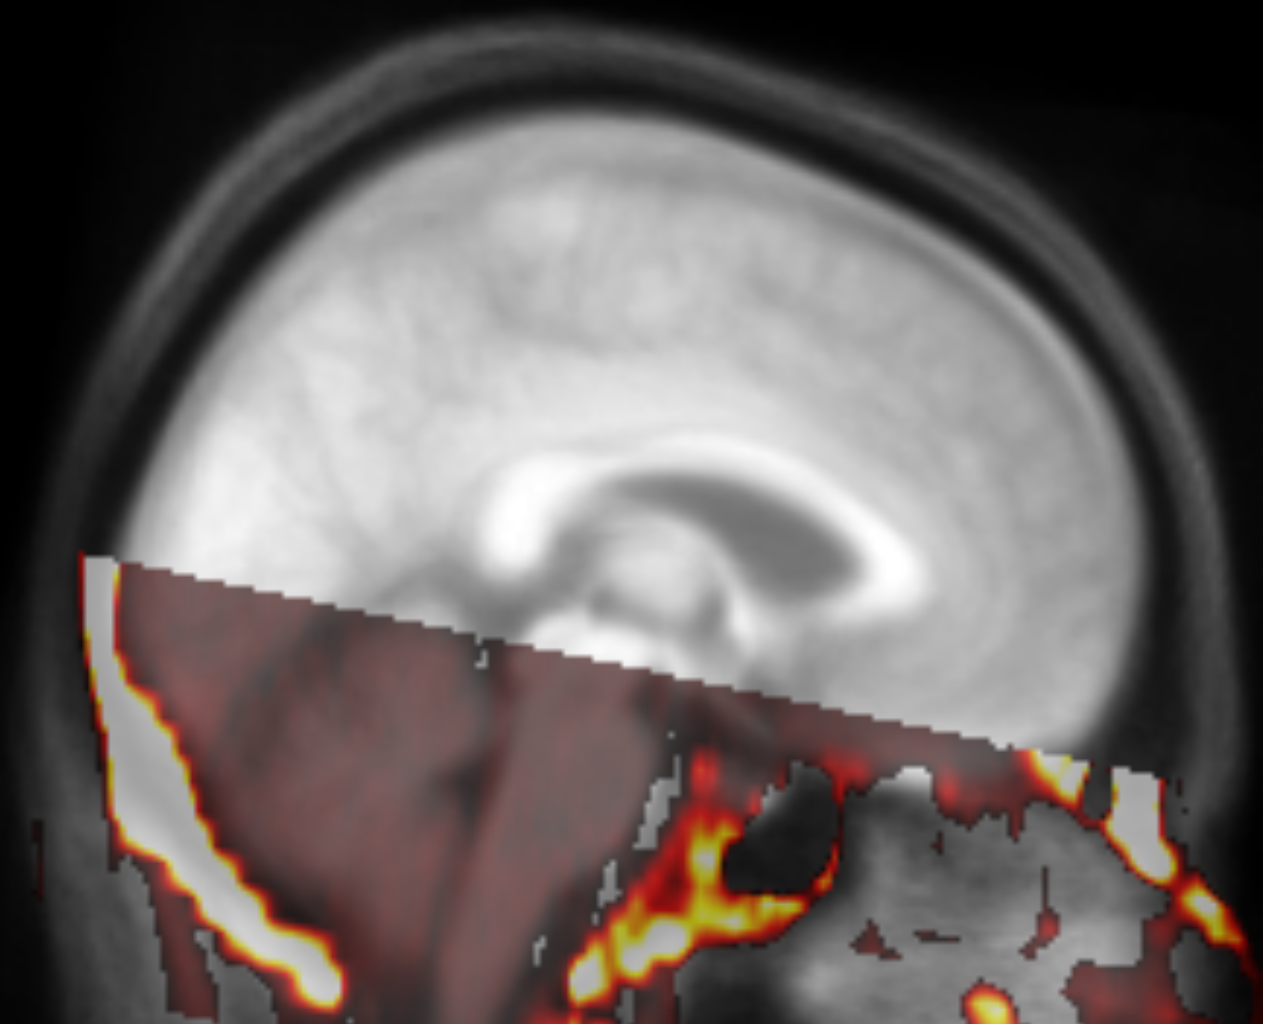

We built custom software to superimpose thresholded ( HU to include calcifications) binary masks derived from the co-registered CT scans to identify anomalies in the alignment with the template and high attenuation values at unexpected locations111https://github.com/bjin96/superimposition-tool. The software provides three views (Figure 2). We use the first view to find anomalies in a large number of CT series. The superimposed image can be inspected in the axial plane and scrolled along the z-axis. Each of the voxels in the view can be selected if any of the binary masks has data at the specific location. If there are multiple binary masks at the selected location (i.e. multiple of the superimposed CT series have values above the threshold at the selected voxel), a single series can be chosen from a list. Upon selection, the alignment of the corresponding binary mask with the MRI template and the original registered series can be examined in the second and third views to inspect the nature of the anomaly and identify possible causes. Found anomalies are documented to a file with a textual comment. The software provides an efficient way to assess a large quantity of registered CT series and find cases with high attenuation values at anomalous locations indicating outliers and inaccurate registrations.